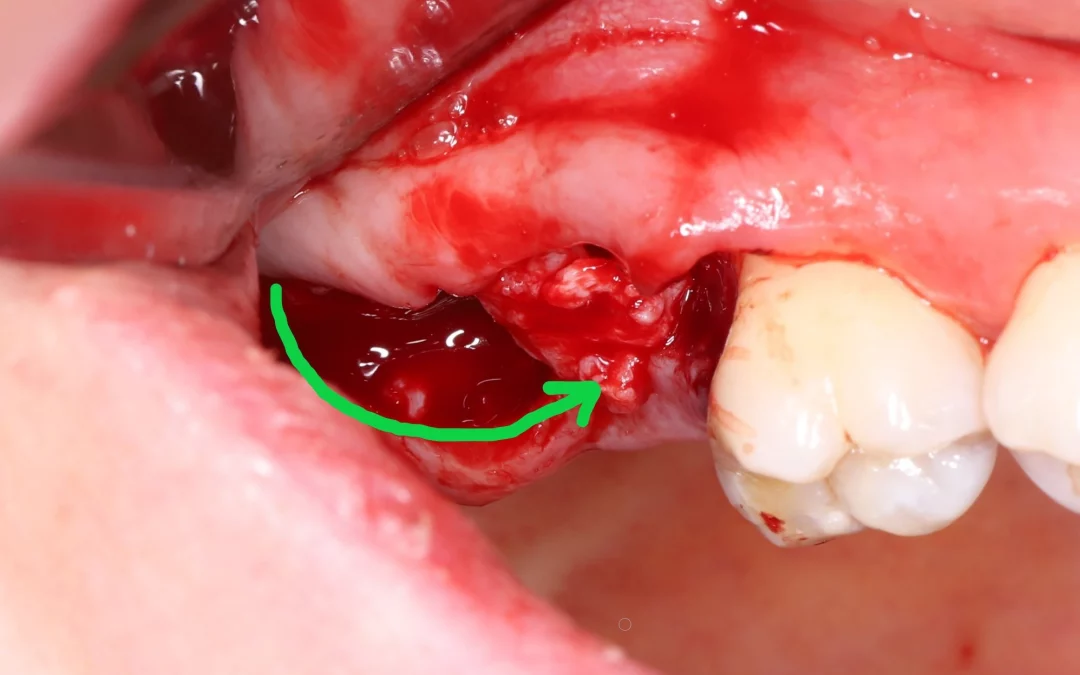

Устранение включенного дефекта зубного ряда на нижней челюсти, который в ходе лечения стал концевым. - Имплантация 4.6, 4.7 MIS C1. - Профилирование кости. - Трансплантат с бугра под вестибулярный лоскут. -...